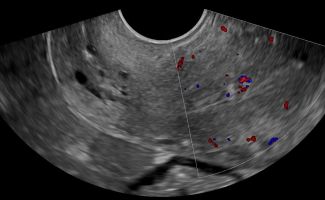

- Ωοθήκες: Η απεικόνιση των ωοθηκών περιλαμβάνει την αξιολόγηση του μεγέθους, της μορφολογίας και της υφής τους. Με το Διακολπικό Υπερηχογράφημα, μπορούν να μετρηθούν τα ωοθυλάκια και να διερευνηθεί η παρουσία συνδρόμου πολυκυστικών ωοθηκών. Οι εστιακές βλάβες στις ωοθήκες, συμπαγείς ή κυστικές, μπορούν να αξιολογηθούν ως καλοήθεις ή ύποπτες, με τη βοήθεια του Έγχρωμου Doppler για την απεικόνιση της αγγείωσης και της ροής του αίματος.